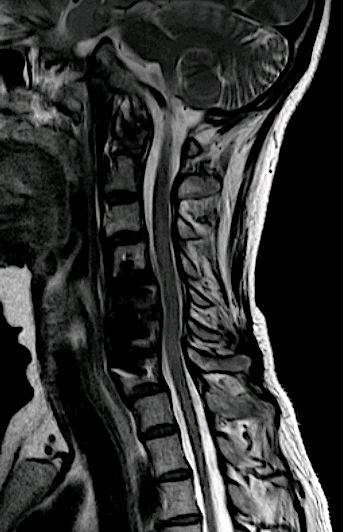

Paciente de 48 años remitida con clínica de mielopatía cervical de meses de evolución e instauración progresiva.

La lesión se ubicaba en el margen anterior de la lámina sin aparente afectación ósea en la RM cervical.

En la imagen coronal se aprecia relación íntima de la lesión con la faceta C7-Th1 que nos hizo sospechar el diagnóstic

Se decidió abordaje posterior, para descompresión y biopsia. El resultado de la AP fue compatible con material degenerativo. La visión quirúrgica confirmó las sospechas de quiste sinovial.